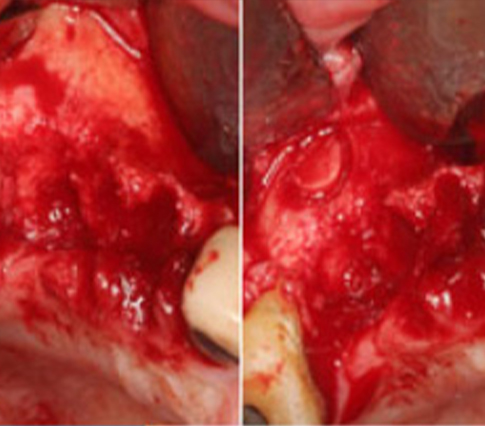

Combined Gbr

#14, 16 : GBR → SST implants placement #46 : SST implants placement #26, 27 : sinus graft + simulaneous SST implants placement #36 : immediate SST implants placement + GBR |

Internal Hex Fixture : SST Type